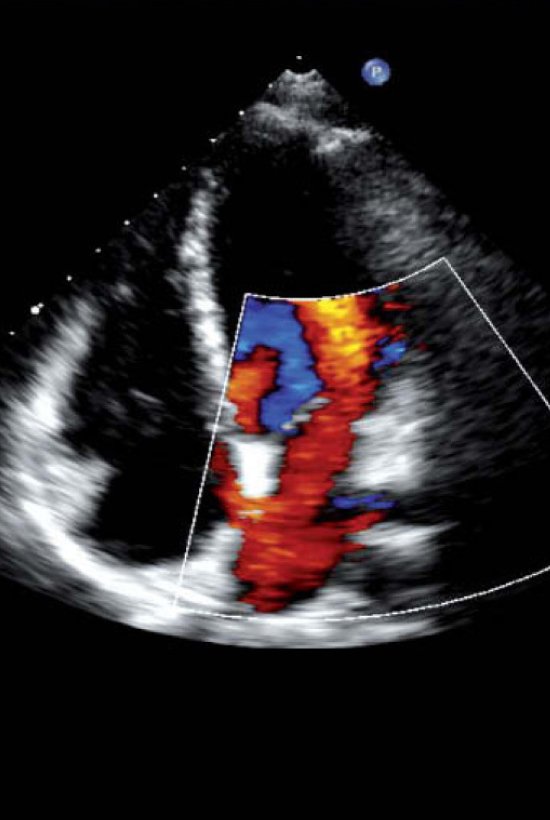

Eco Doppler Cardíaco